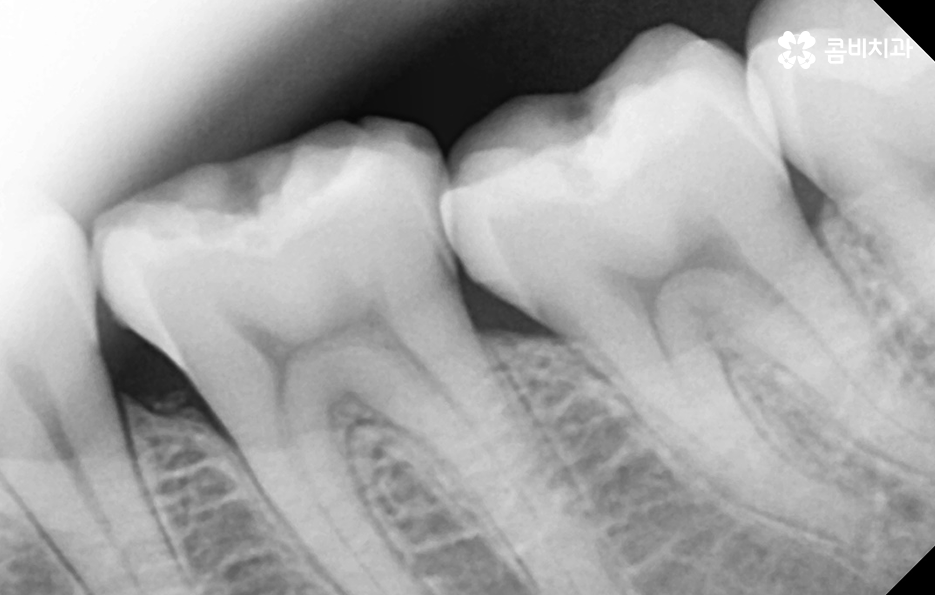

어금니 레진으로 치료 했던 부위의 주변에 검게 변색되었어요. 그리고 주변이 깨졌어요

보철 치료 후의 2차 충치 문제는 사실 아말감 뿐 아니라 어떤 보철물이든지 주의해야 할 점이며 보철물 자체나 주변 치아가 깨지거나 마모되어 2차 충치가 진행되기도 하지만 오래된 보철물의 접착제가 녹아서 2차 충치로 이어지는 경우도 있기 때문에 보철물의 수명과 교체 주기에 따라서 주기적으로 재치료를 하는 것이 2차 충치에 대한 우려를 예방하는데도 중요할 수 있어요

레진은 앞니 부터 어금니까지 치아 손상의 초기에 광범위하게 활용되고 있지만 특히 어금니 레진의 경우에는 교합면이나 특히 강하게 저작기능에서 압력을 받는 경우에 자주 깨지고 탈락 될 경우에는 인레이 치료를 하는 것이 적합할 수 있습니다

특히 치아 신경치료로 이어지거나 치아 뿌리 쪽에 충치가 깊어지면 치아 수명이 급격히 저하되고 발치로도 이어질 수 있다는 점에서 현재 어금니 레진 교체에 대한 고민을 한다면 현재 치아 상태에 적합한 치료도 제때 잘 받아주시길 바라며 무엇보다 보철물 관리에도 힘써서 비슷한 문제가 재발하지 않도록 주의하시길 바라고 있어요